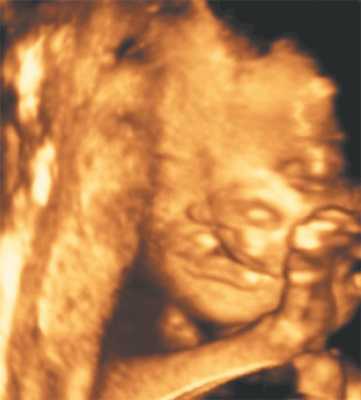

Наиболее впечатляющие изображения, которые можно получить в акушерской практике - портреты плода перед наступлением родов. Наилучшие результаты достигаются, если в ходе объемного сканирования профиль плода находится в центральном положении. Угол просмотра в 60 градусов является оптимальным, при котором можно получить полное изображение лица плода. Выбор слишком маленького угла может привести к "потере" частей лица, а артефакты, вызванные движениями, могут возникнуть при высокой линейной плотности, которую выбирают, чтобы добиться хорошего разрешения.

Трехмерное изображение лица плода может также способствовать установлению контакта между матерью и ребенком подобно первому прослушиванию сердцебиений (рис. 1).

Рис. 1. Нормальное лицо плода.

Цель 3D-ультразвукового исследования состоит в создании объемного изображения в отличие от двухмерного метода, создающего плоскостные сечения [6, 11]. Объемная картина получается при сканировании смежных сечений — это объем пространства пирамидальной формы (рис. 3, 4).

Рис. 3. Плод, 31 неделя, 3D-ультразвуковое исследование / Fig. 3. Fetus, 31 weeks, 3D